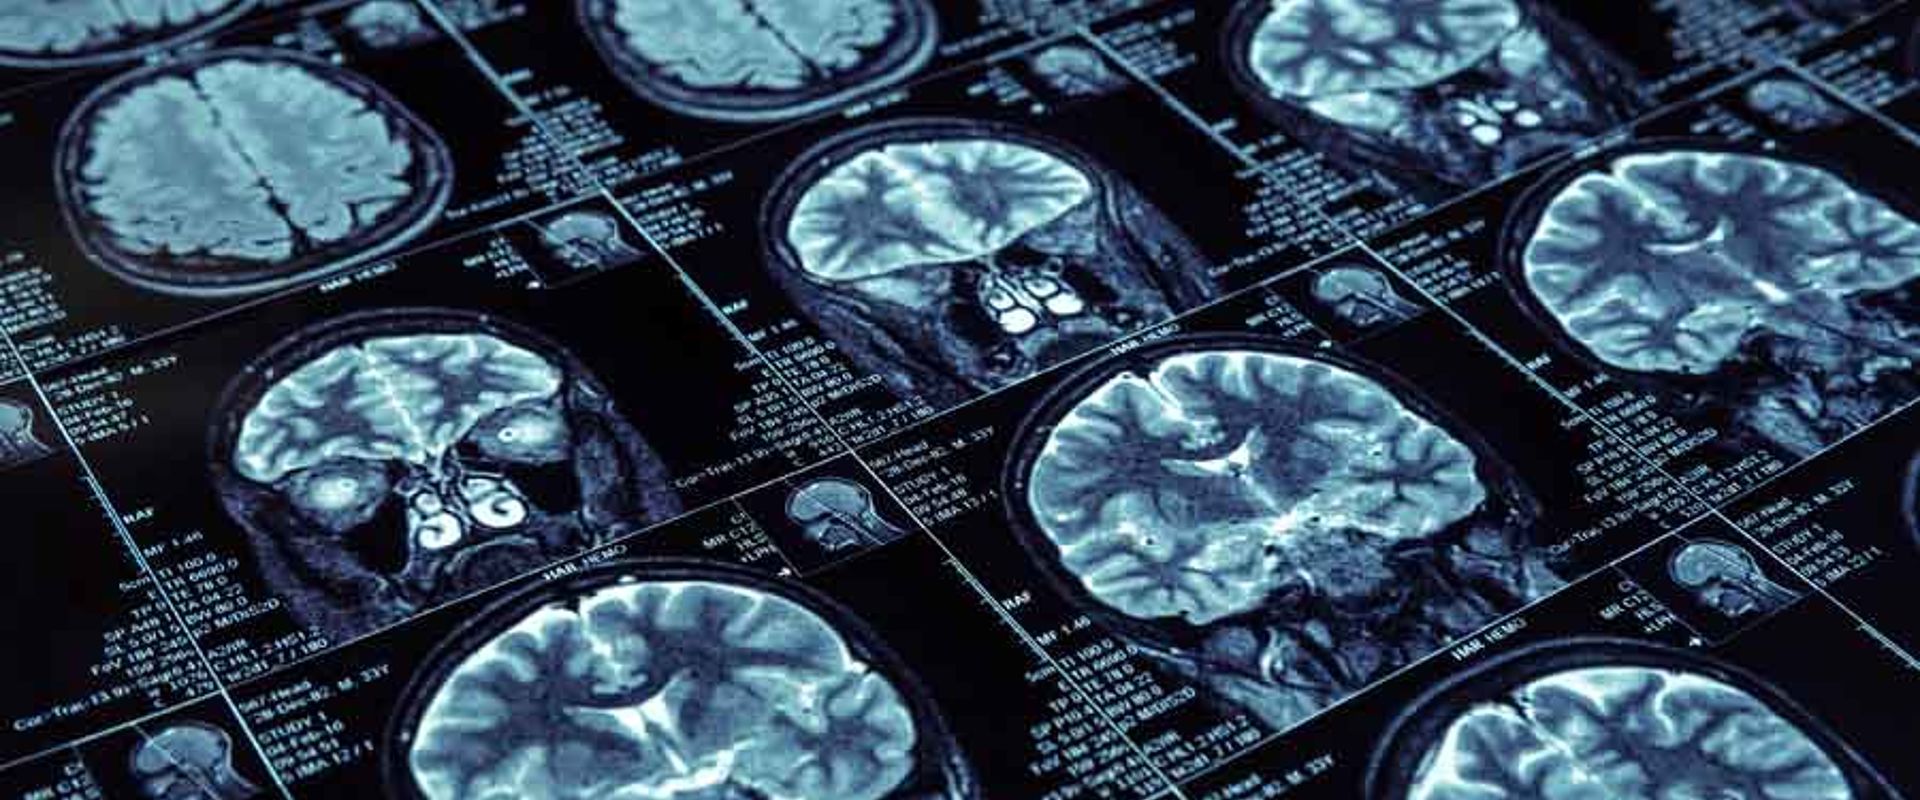

High resolution brain scans

Magnetic Resonance Imaging (MRI) is a highly effective technique for peering into the body and looking for evidence of serious problems such as tumours and damaged blood vessels. Over 30 million patients already have MRI examinations annually across the EU, and now higher resolution 7T MRI scanners are able to offer even better early disease diagnosis and the potential for detecting Alzheimer’s, Parkinson’s and Multiple Sclerosis.

Currently hospitals use MRI scanners with 1.5 or 3 tesla (T) magnetic field strength - devices shown to be safe for hospital use. For 7T MRI to be introduced into routine clinical use, it is necessary for MRI manufacturers and hospitals to have confidence in staff and patient safety.

MRI machines apply a high magnetic field to the body and the greater the magnetic field, the greater the resolution of the images. But an MRI scanner is more than just a strong magnet; it also exposes the patient to radio waves so powerful, patients need constant direct supervision to prevent injury. The stronger the magnet, the higher the frequency of these radio waves and the more complicated their interaction with the patient’s body. As a result, computer simulations are now required to determine the patient’s safety where robust and reliable hardware had previously been adequate. New measurement tools are needed to evaluate simulations and enable demonstration that the radio waves from 7T MRI are safe to use.

The current IEC standard facilitates CE marking for 7T MRI scanners based on conformance to EU regulatory requirements. This now makes these ultra-high resolution MRI imaging machines available for clinical use, albeit with restrictions. Clinics will now have a more powerful imaging tool capable of enabling earlier diagnosis of serious and degenerative brain diseases and other treatable conditions creating the potential for earlier life-changing treatments. Future editions of the IEC standard will waive these current restrictions and broaden the range of 7T MRI uses in clinical medicine.